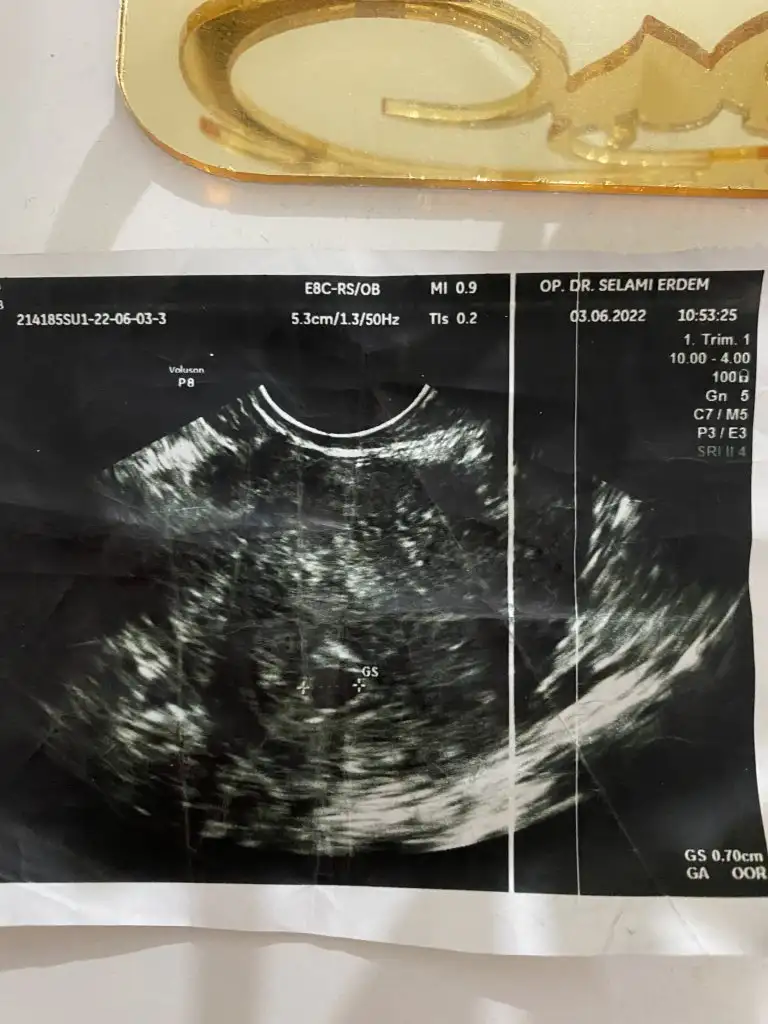

4-8-12 haftalık ultrason görüntüleri bebeğimin hepsi karından cinsiyetini tahmin eder misiniz acaba

Herkese hayırlı olsun, sağlıklı olsunda insan merak ediyor işte banada yorum yapar mısınız 6 haftalık vajinal ultrason